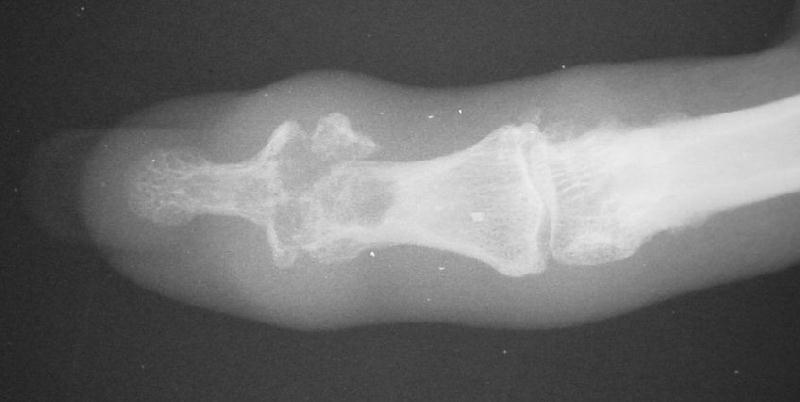

Distal interphalangeal erosive osteoarthritis severe enough that the diagnosis of giant cell or other tumor was suspected. Fortunately, no tumor was encountered at surgery.

Final implant radiographs.

Xrays one year out.